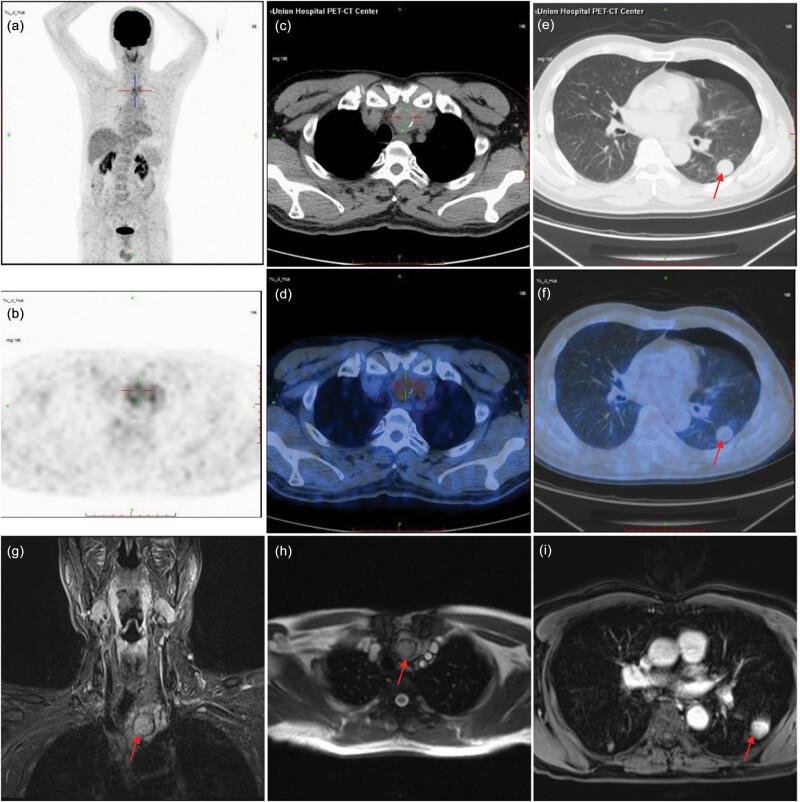

Thymomas and thymic carcinomas are rare and primary tumors of the mediastinum which is derived from the thymic epithelium. Thymomas are the most common primary anterior mediastinal tumor, while ectopic thymomas are rarer. Mutational profiles of ectopic thymomas may help expand our understanding of the occurrence and treatment options of these tumors. In this report, we sought to elucidate the mutational profiles of two ectopic thymoma nodules to gain deeper understanding of the molecular genetic information of this rare tumor and to provide guidance treatment options. We presented a case of 62-year-old male patient with a postoperative pathological diagnosis of type A mediastinal thymoma and ectopic pulmonary thymoma. After mediastinal lesion resection and thoracoscopic lung wedge resection, the mediastinal thymoma was completely removed, and the patient recovered from the surgery and no recurrence was found by examination until now. Whole exome sequencing was performed on both mediastinal thymoma and ectopic pulmonary thymoma tissue samples of the patient and clonal evolution analysis were further conducted to analyze the genetic characteristics. We identified eight gene mutations that were co-mutated in both lesions. Consistent with a previous exome sequencing analysis of thymic epithelial tumor, was also observed in both mediastinal lesion and lung lesion tissues. We also evaluated the intratumor heterogeneity of non-silent mutations. The results showed that the mediastinal lesion tissue has higher degree of heterogeneity and the lung lesion tissue has relatively low amount of variant heterogeneity in the detected variants. Through pathology and genomics sequencing detection, we initially revealed the genetic differences between mediastinal thymoma and ectopic thymoma, and clonal evolution analysis showed that these two lesions originated from multi-ancestral regions.

胸腺瘤和胸腺癌是源自胸腺上皮的罕见纵隔原发性肿瘤。胸腺瘤是最常见的原发性前纵隔肿瘤,而异位胸腺瘤则较为罕见。异位胸腺瘤的突变谱可能有助于拓展我们对这些肿瘤发生及治疗选择的理解。在本报告中,我们试图阐明两个异位胸腺瘤结节的突变谱,以更深入了解这种罕见肿瘤的分子遗传信息,并为治疗选择提供指导。我们报告了一例62岁男性患者,术后病理诊断为A型纵隔胸腺瘤和异位肺胸腺瘤。在进行纵隔病变切除和胸腔镜肺楔形切除术后,纵隔胸腺瘤被完全切除,患者术后恢复,至今检查未发现复发。对该患者的纵隔胸腺瘤和异位肺胸腺瘤组织样本进行了全外显子组测序,并进一步进行克隆进化分析以分析遗传特征。我们在两个病变中鉴定出八个共同突变的基因突变。与先前对胸腺上皮肿瘤的外显子组测序分析一致,在纵隔病变和肺病变组织中也均观察到[此处原文缺失相关内容]。我们还评估了非沉默突变的肿瘤内异质性。结果显示,在检测到的变异中,纵隔病变组织具有更高程度的异质性,而肺病变组织的变异异质性相对较低。通过病理学和基因组测序检测,我们初步揭示了纵隔胸腺瘤和异位胸腺瘤之间的遗传差异,克隆进化分析表明这两个病变起源于多个祖先区域。